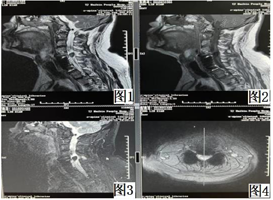

辅助检查:2009年11月3日北京大学第三医院MR检查报告单:C5椎体附件、C6及T3、4椎体多发骨折,继发骨性椎管狭窄;C5、6椎体脱位;脊髓水肿。2010年9月10日北京博爱医院MR报告:C5-7骨折椎体前路内固定术后,C5-7骨折椎体水平脊髓损伤。2022年5月10日天津市滨海新区海滨人民医院复查颈椎MRI示:(1)颈5-7锥体术后改变,内固定置入术后。(2)颈5锥体后缘低信号影,颈髓受压结构不清(图1,图2,图3,图4)。